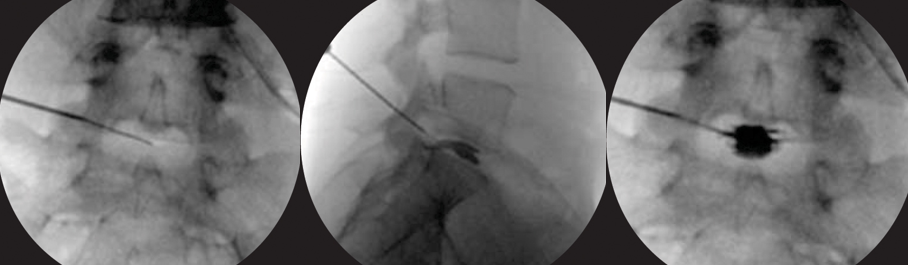

放置导丝(扩张软组织)用锋利的小手术刀在进针点皮肤切开一个大约8 mm的切口。沿着导丝向小关节方向插入导杆。在导杆外沿着导杆逐级放套管向外扩张软组织。

扩椎间孔骨钻套在套管的外边。沿着套管放置骨钻,去掉小关节远端增生的骨质,扩大椎间孔。

使用骨钻时,用C型臂从前后和侧面确定器械和骨钻顶端的位置。骨钻的最前端不能超过中线,以避免刺激或损伤神经。

放置工作套管(工作通道)独特设计的套管顶端可以保护神经根免遭损伤

用C型臂确定工作套管放置的位置。正确的位置应该是放在神经根下方,椎间盘水平,顶端正好在中线,开口朝向突出的髓核。

放置椎间孔镜连接椎间孔镜到光源和摄像机。打开光源,调节白平衡,达到最佳彩色效果。把椎间孔镜放入工作套管。调节合适的水流量和压力对取得良好效果很重要。